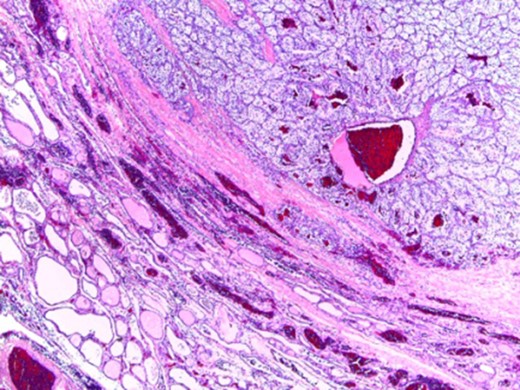

In microscopic evaluation the tumor had a predominantly ‘clear cell’ morphology, typical of RCC as shown in Figs 2 and 3.

Normal thyroid tissue on the lower left corner; clear cells in the upper right quadrant.